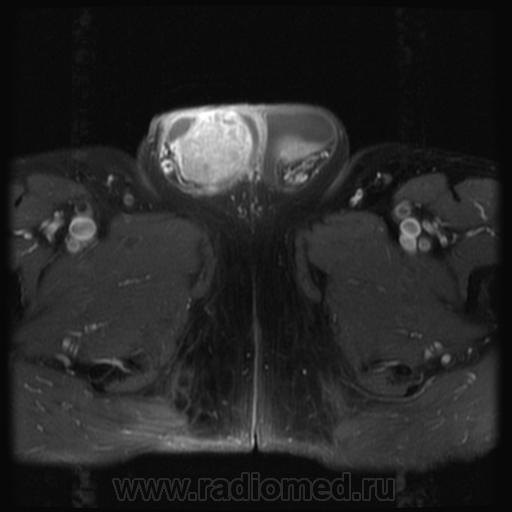

семинома?

Считаю, что семинома - не самый вероятный вариант, т.к. структура опухоли достаточно неоднородная, есть распространение на придаток и границы четкие.

Могу предположить, неоплазию правого яичка.

Я в заключении вынес на первый ряд карциному яичка.